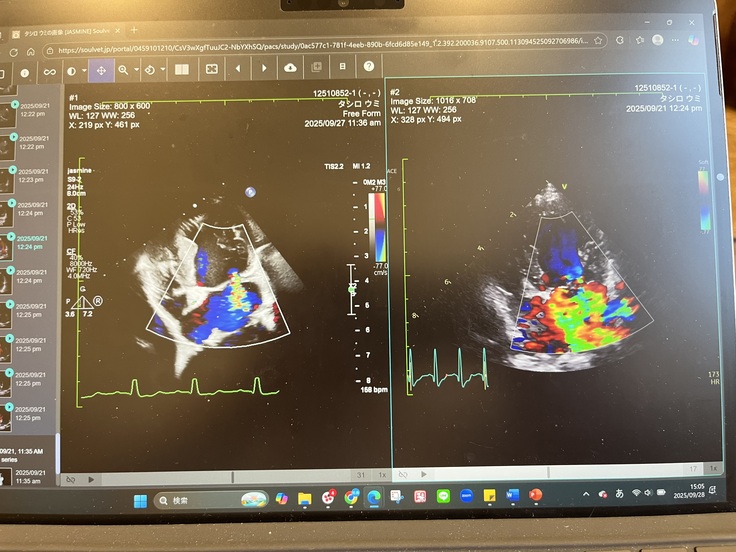

◆ 逆流

逆流は一筋残っているとのことでした。

青海の場合はもともと逆流が強かったため、今後も強心剤の服用を続ける方針です。

右が術前、左が術後 緑が逆流です。